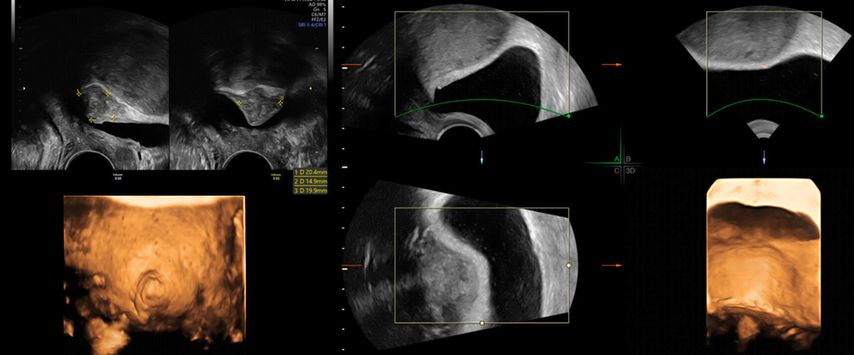

In unklaren Fällen, in denen die äussere Uteruskontur in der MPR nicht eindeutig zu sehen ist und so die Unterscheidung zwischen einem Uterus (sub-)septus und einem Uterus bicornis schwierig ist, hilft TUI bei der Differenzialdiagnose (Abb. 5 und 6).

Abb. 6: Uterus bicornis. Ist die äussere Uteruskontur in der MPR nicht eindeutig zu erkennen, hilft TUI (rechts)